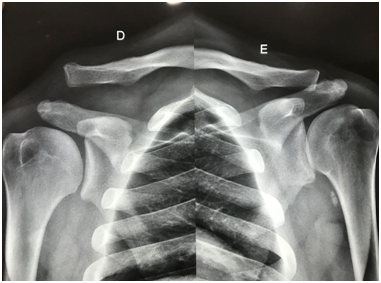

This retrospective study comprised the review of medical records of 32 patients diagnosed with acromioclavicular dislocation, who underwent surgery using the modified Weaver-Dunn technique by the Orthopedics and Traumatology service of a tertiary referral hospital in northeastern Brazil between April 2011 and January 2016. The preoperative evaluation of such patients was carried out using radiographs AP shoulder radiograph of the ipsilateral and contra lateral sides of the injury.

The minimum follow-up time was 06 months, with follow-up appointments after 2, 6, 12, and 25weeks.After surgery, the operated limb was immobilized in a Velpeau sling for six weeks. As part of the rehabilitation program, pendulum movements and internal and external rotations at zero degrees were authorized immediately after surgery. Passive and active movements (to gain range of motion) started six weeks after the procedure. Each follow-up appointment consisted of a radiological control similar to that in the preoperative stage (Figure 1) and physical examinations. The medical team chose the UCLA score as the criterium for evaluation due to its practicality and the inclusion of the patient’s satisfaction criterium, with the results being interpreted using Ellman criteria.

Figure 1 Preoperative radiograph of both shoulders.